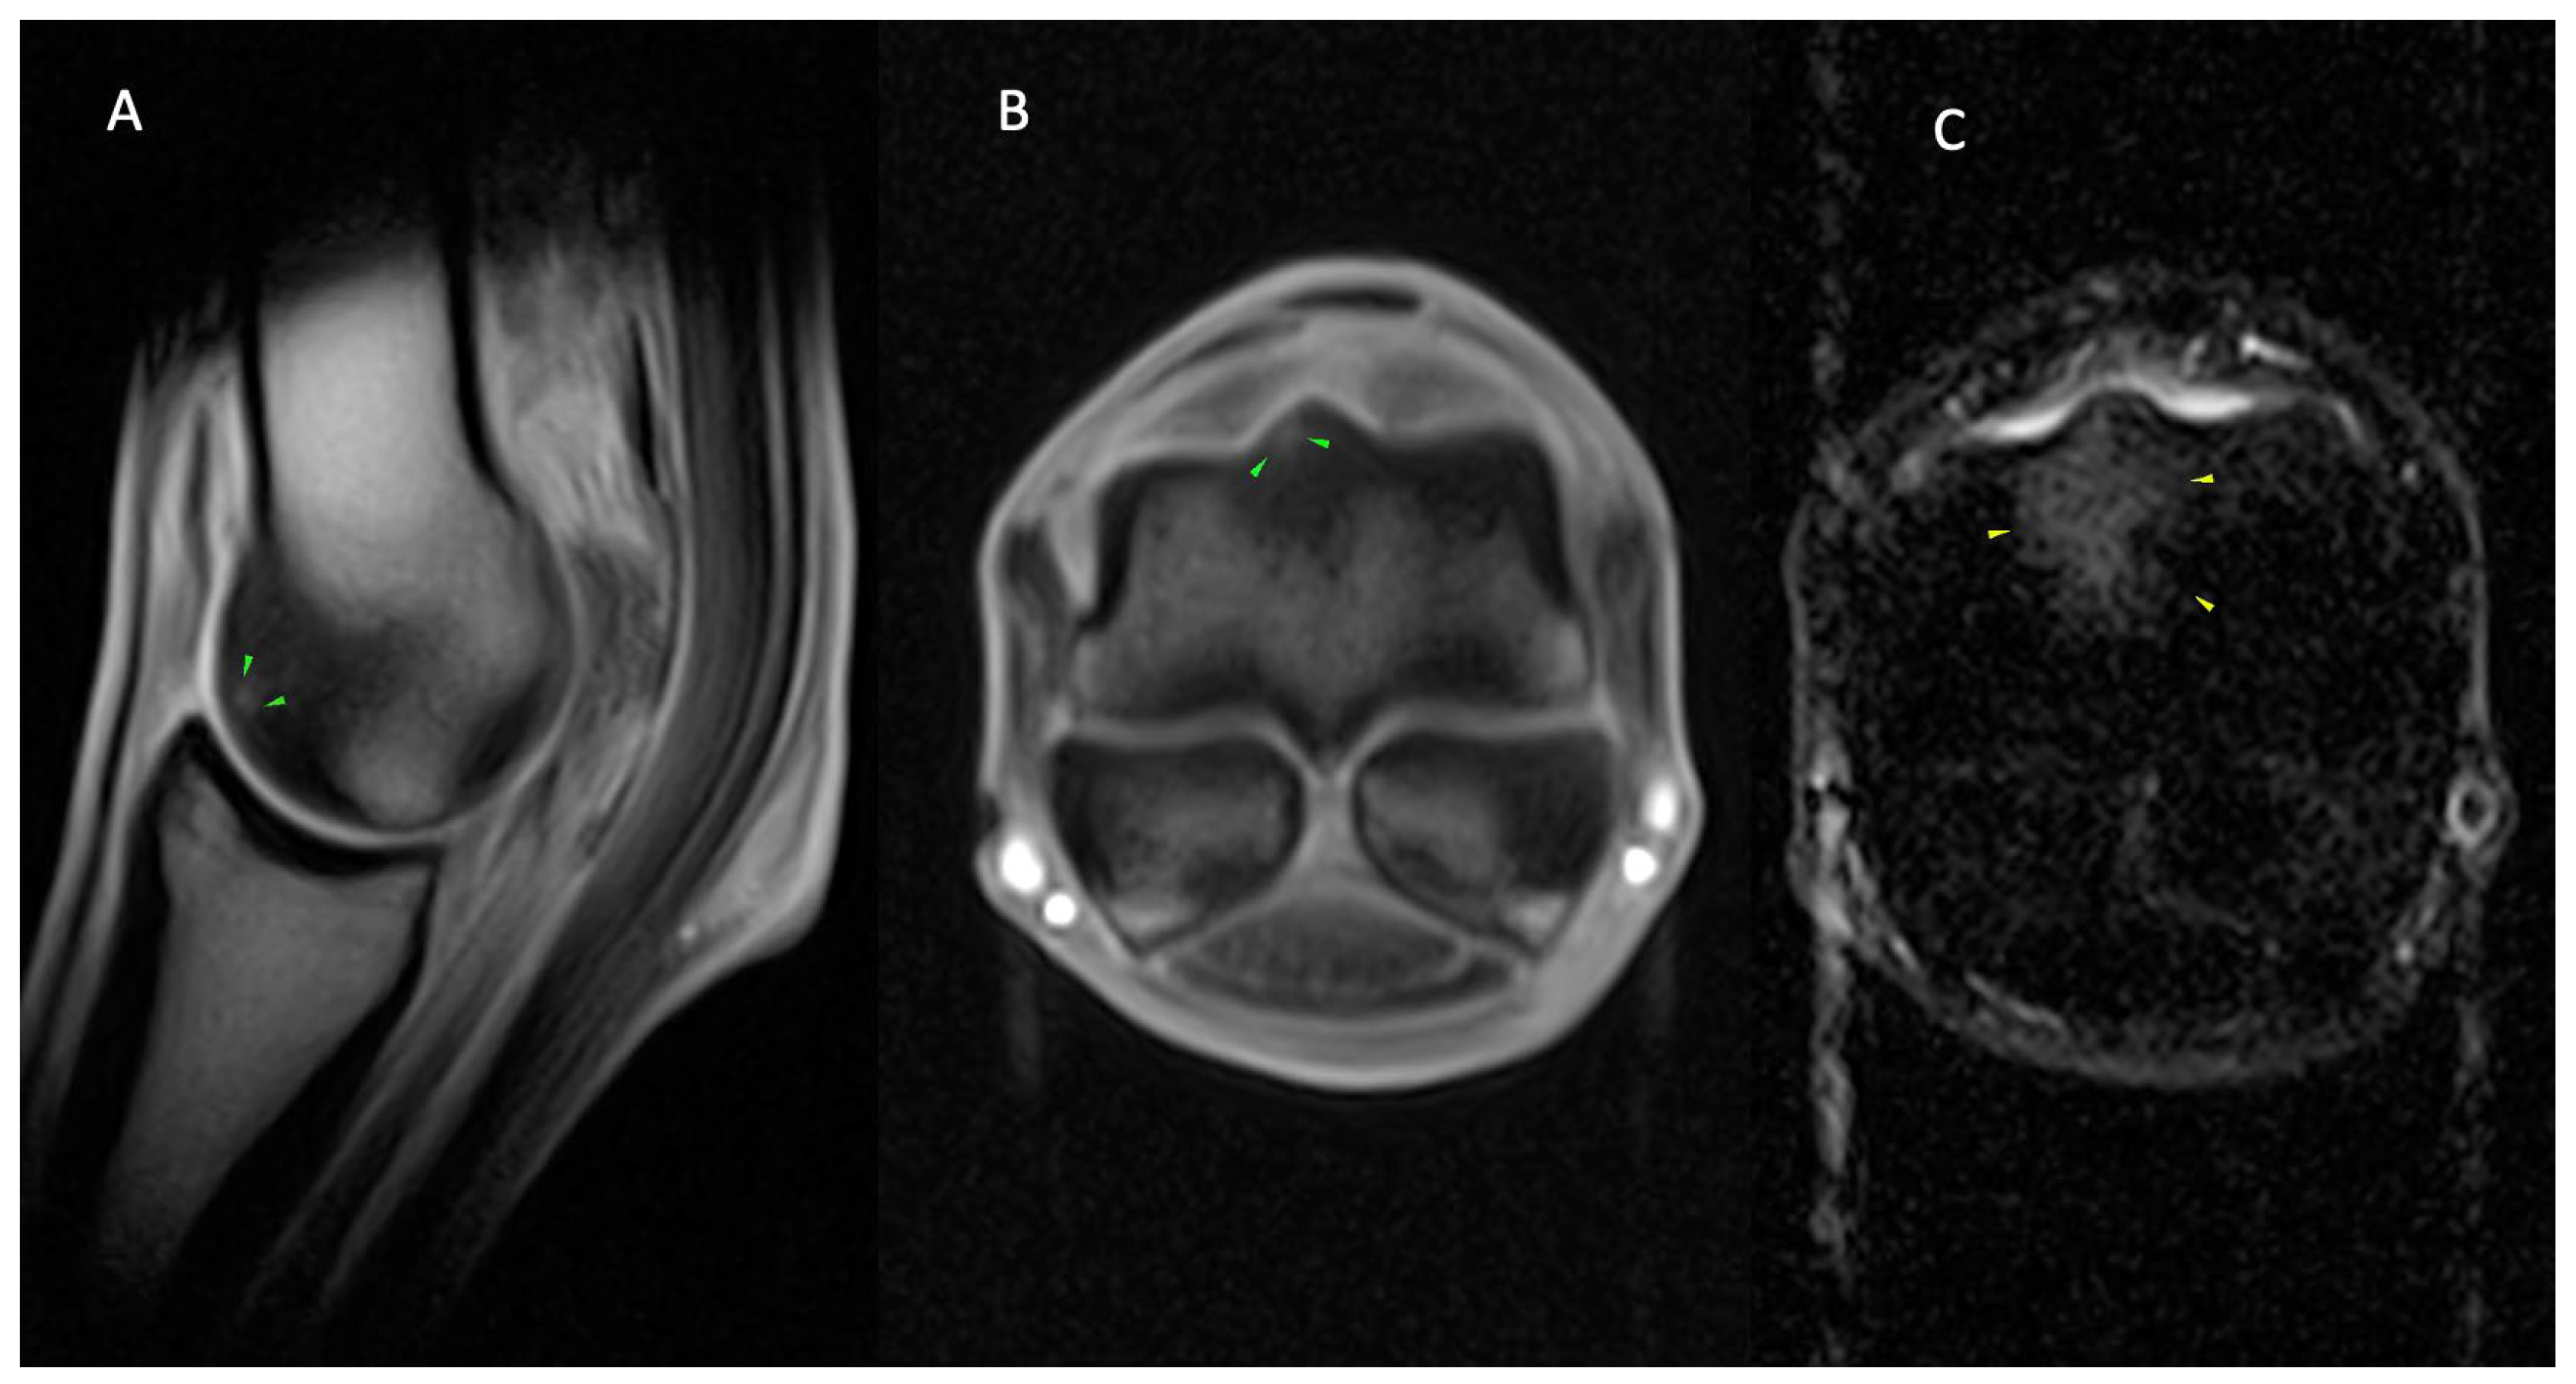

3.2.1. Osseous Pathology

3.2.2. Joint Pathology

3.2.3. Soft Tissue Pathology